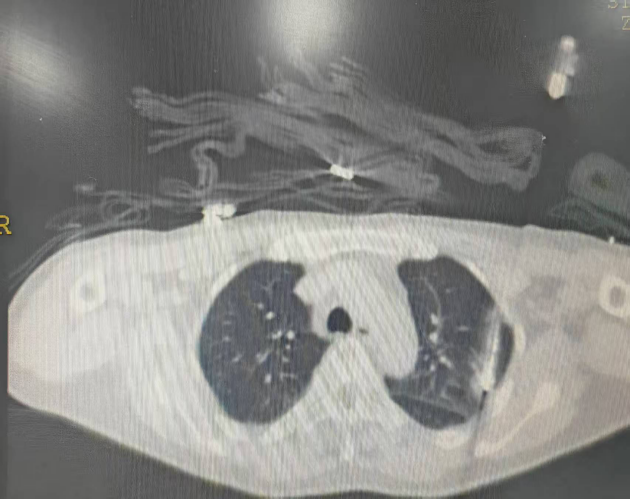

CT引导下消融针穿刺进入肿瘤